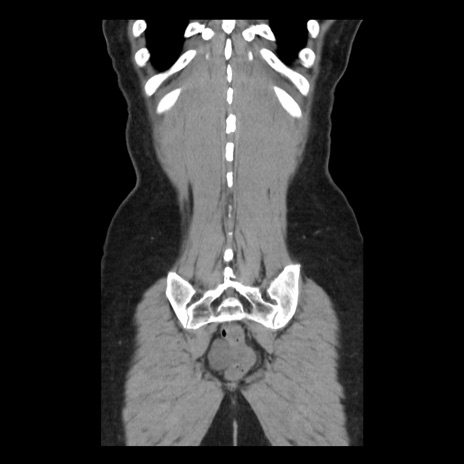

症例10(冠状断像)

症例

【症例】 50歳代女性

【主訴】 腹痛

【現病歴】前日生レバーを食べた。今朝に排便あり。 昼前に突然発症の腹痛を生じ、当院救急外来を受診した。

【既往歴】 子宮筋腫にてで子宮全摘後

【身体所見】 意識清明、腹部:平坦、軟、下腹部やや左を中心に圧痛・反跳痛あり、筋性防御あり

【データ】WBC 7800、CRP 0.07